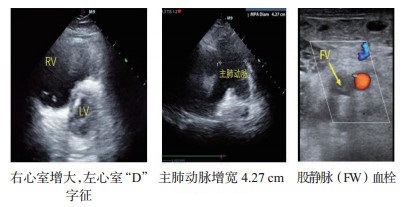

B、心腔大小主要观察左右心比例,右心室内径与左心室内径比值。心腔均明显变小,甚至出现“kiss sign”等超声表现,需评估患者容量状态,在实施ECMO前做好容量准备,以免上机运行后出现干抽、抖管等情况。若右室舒张末内径大于左室舒张末内径者,结合临床并寻找其他直接或间接导致右心压力增加的证据和原因(图 4)。当某一腔室异常增大时,需留意此腔室相关瓣膜功能,并对瓣膜功能进行简单超声评估。

| 图 4 肺栓塞超声表现 |

E、肺动脉发现右心增大、三尖瓣反流等疑似右心室后负荷增加的证据者,需额外观察肺动脉主干直径、有无血栓,观察肺动脉血流及测量肺动脉瓣反流血流速度等指标,寻找肺栓塞等梗阻性休克证据(图 4)。